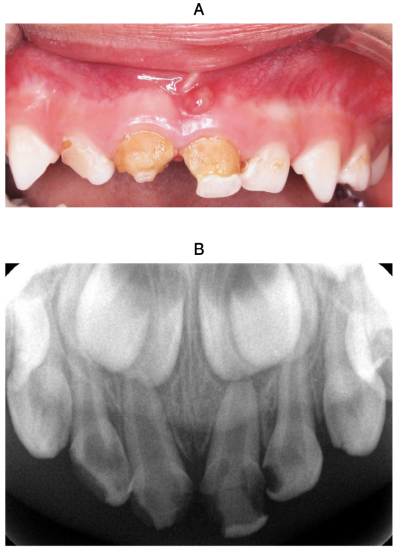

4歳の女児。上顎乳前歯部の審美不良を主訴として来院した。1週前から上顎右側乳中切歯の自発痛と上顎左側乳中切歯の歯肉の腫脹に気付いたがそのままにしていたという。初診時の口腔内写真とエックス線写真を別に示す。上顎両側乳中切歯の検査結果の一部を表に示す。

A⏌ - ⎿A